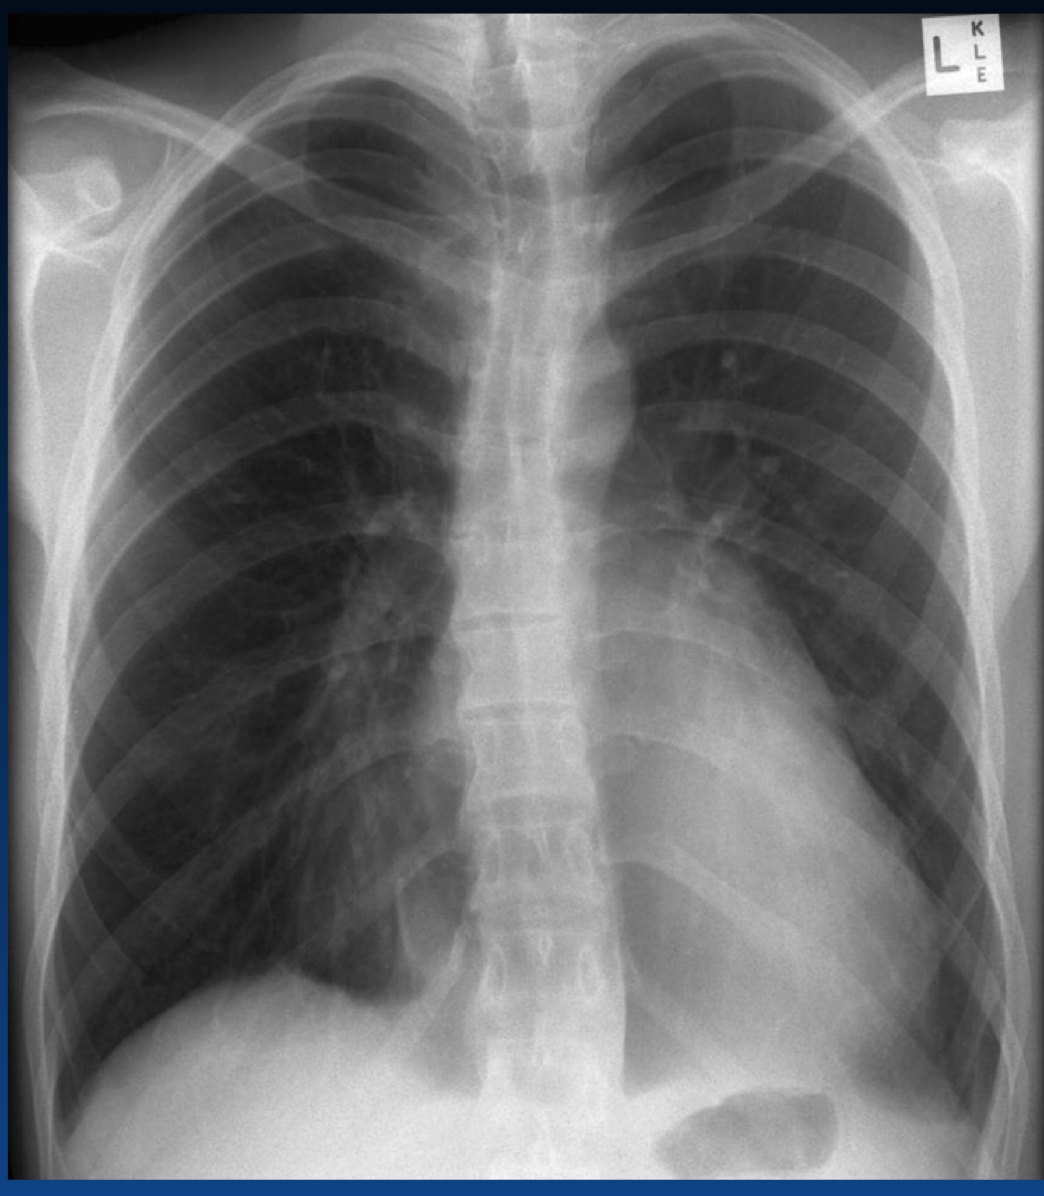

Right side is normal

Label the heart chambers